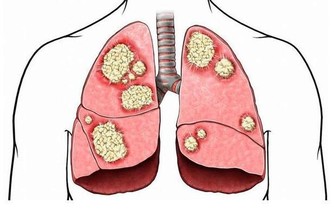

膀胱經預防和主治的疾病:呼吸系統:感冒、發燒、哮喘、肺炎;

若聚毒難散,體內必生瘀積腫物;若此處常通,則癌癥不生,惡疾難成。